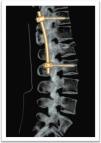

El tratamiento quirúrgico de la fractura en L2 fue con fijación de T12 a L3 con sistema de tornillos transpediculares Medtronic®, Legacy®, sin fijación de los pedículos de L1 por la diastematomielia (figs. 4 y 5).

Una vez diagnosticada la disrafia espinal, se realizó la cirugía respetando el segmento de la diastematomielia puesto que los pedículos son pequeños y displásicos, lo que obligó a realizar el anclaje de los tornillos transpediculares en el segmento superior adyacente7,8. La evolución del paciente a 1 año fue satisfactoria.